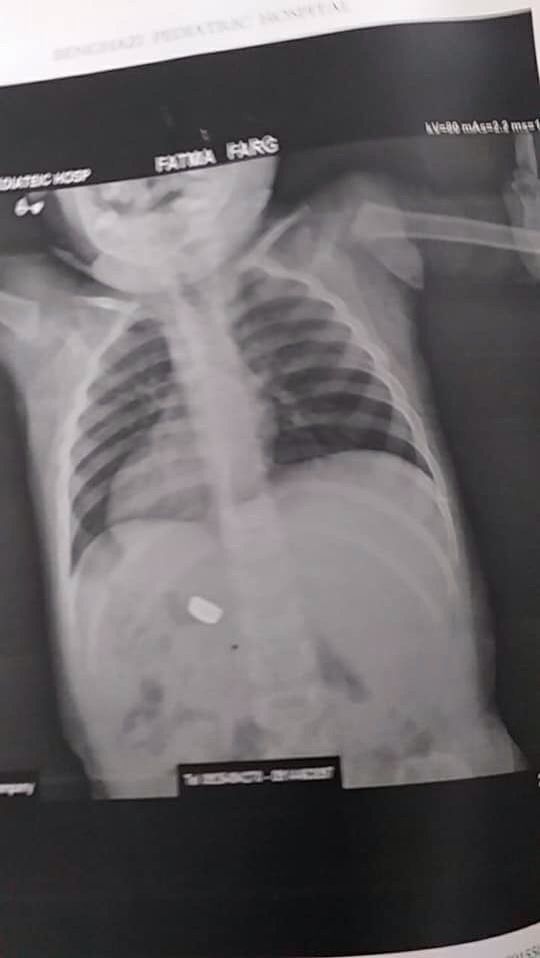

Girl swallowed

Girl swallowed battery ... where battery can exist now